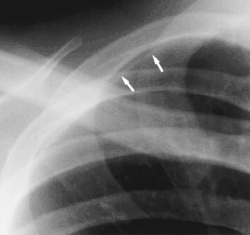

- Clavicular companion shadow is a thin soft-tissue stripe along the upper edge of the clavicle.[1]

- Rib companion shadows parallel the ribs and measure 1–5 mm in diameter project adjacent to the inferior and inferolateral margins of the first and second ribs and the axillary portions of the lower ribs. These companion shadows of the first and second ribs occur in 35% and 31% of the population, respectively. Rib companion shadows represent the fat and muscles in the intercostal space. The shadows that accompany the ribs may mimic pleural and lung disease.[2]